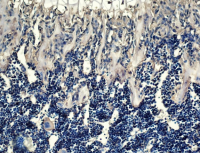

细胞库 / 细胞培养、试剂、技术服务

SCI文献引用优选产品